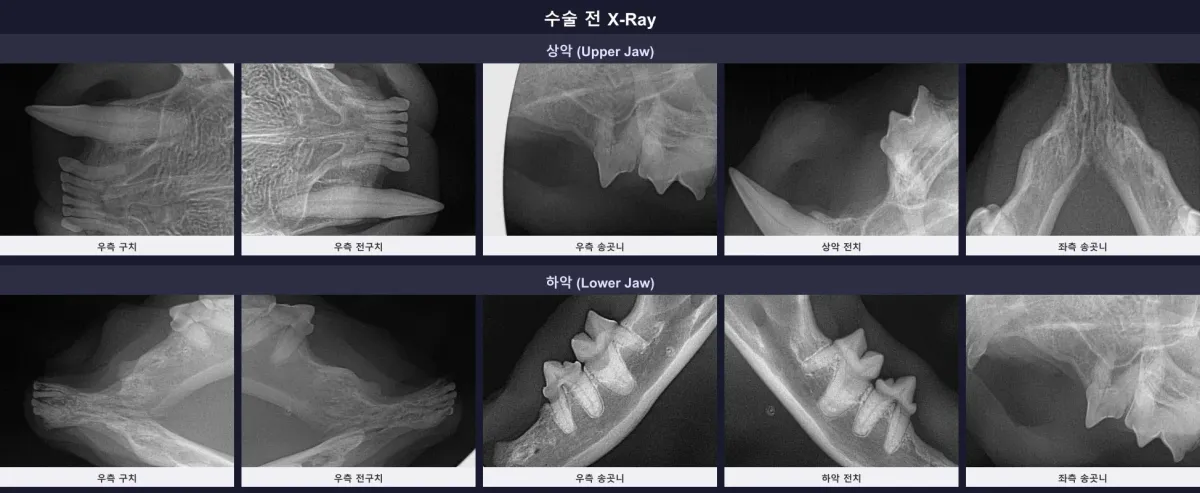

타병원에서 전발치를 받았지만 통증이 지속된 고양이. 광주 금호동물병원의 치과 전용 CT와 엑스레이로 다수의 잔존 치근을 발견하고 안전하게 제거한 고난도 재수술 증례를 확인하세요. 잔존 치근의 위험성부터 수술 후 회복까지 상세히 안내합니다.